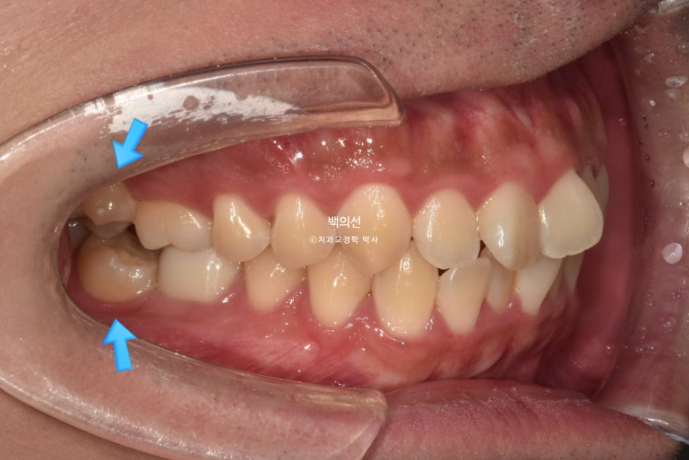

특히 아래 두번째 큰어금니는 쓰러져 있습니다.

노란선이 쓰러져 있는 큰어금니죠. 사랑니를 빼고 세워야 합니다.

문제의 쓰러진 큰어금니는 앞의 큰어금니에 걸려있는 상태로, 인비절라인 투명교정장치 만으로 세우기는 힘들어요.

클리피씨와 같은 브라켓을 붙이고 철사의 힘을 빌려야 합니다.

환자분은 투명교정을 원했기 때문에 투명교정장치 제작 전 쓰러진 어금니와 가위교합을 먼저 개선해놓고, 나머지 앞니 삐뚠 부분은 인비절라인 라이트로 해결하기로 했습니다.